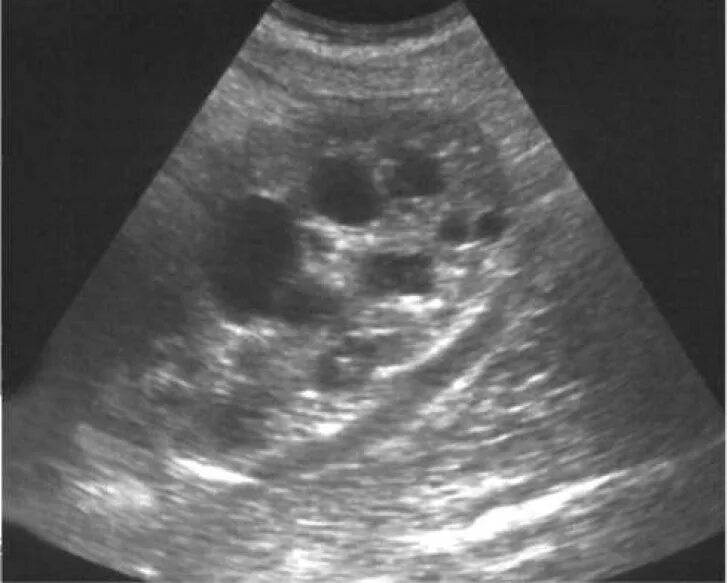

Мультикистозная почек плода